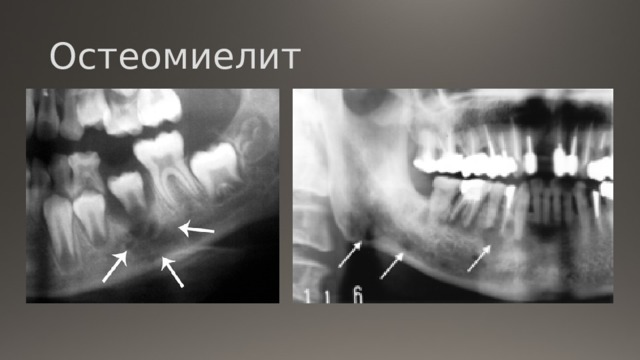

Рентгеновские снимки посттравматического остеомиелита челюсти: Медицинские случаи

Раздел: Образы вокруг